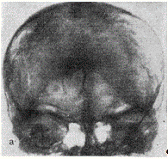

К местным изменениям могут быть отнесены деструкции костей черепа и позвоночника и их отверстий, связанные с давлением прилежащих к ним опухолевых узлов. Развитие нейрофиброматозных узлов, связанных с черепномозговыми нервами, преимущественно VIII и иногда V пары, сопровождается деструкцией костной ткани на месте расположения опухолей. Так, при наличии неврином слуховых нервов внутренние слуховые проходы обычно резко расширены: при двусторонних невриномах - с двух сторон (рис. 1), при односторонних - с одной. Верхушки пирамид, при этом истончены и деструктированы (рис. 2). Расширение внутреннего слухового прохода и деструкция (узура, порозность) верхушки пирамиды височной кости, которые всегда можно увидеть на прицельных рентгенограммах этой области, являются одним из основных краниографических. симптомов невриномы VIII нерва.

Рис. 1. Больной Л., 14 лет, с двусторонней невриномой VIII нерва. Резкое расширение внутренних слуховых проходов (снимки пирамид ви­сочных костей по Stenvers).